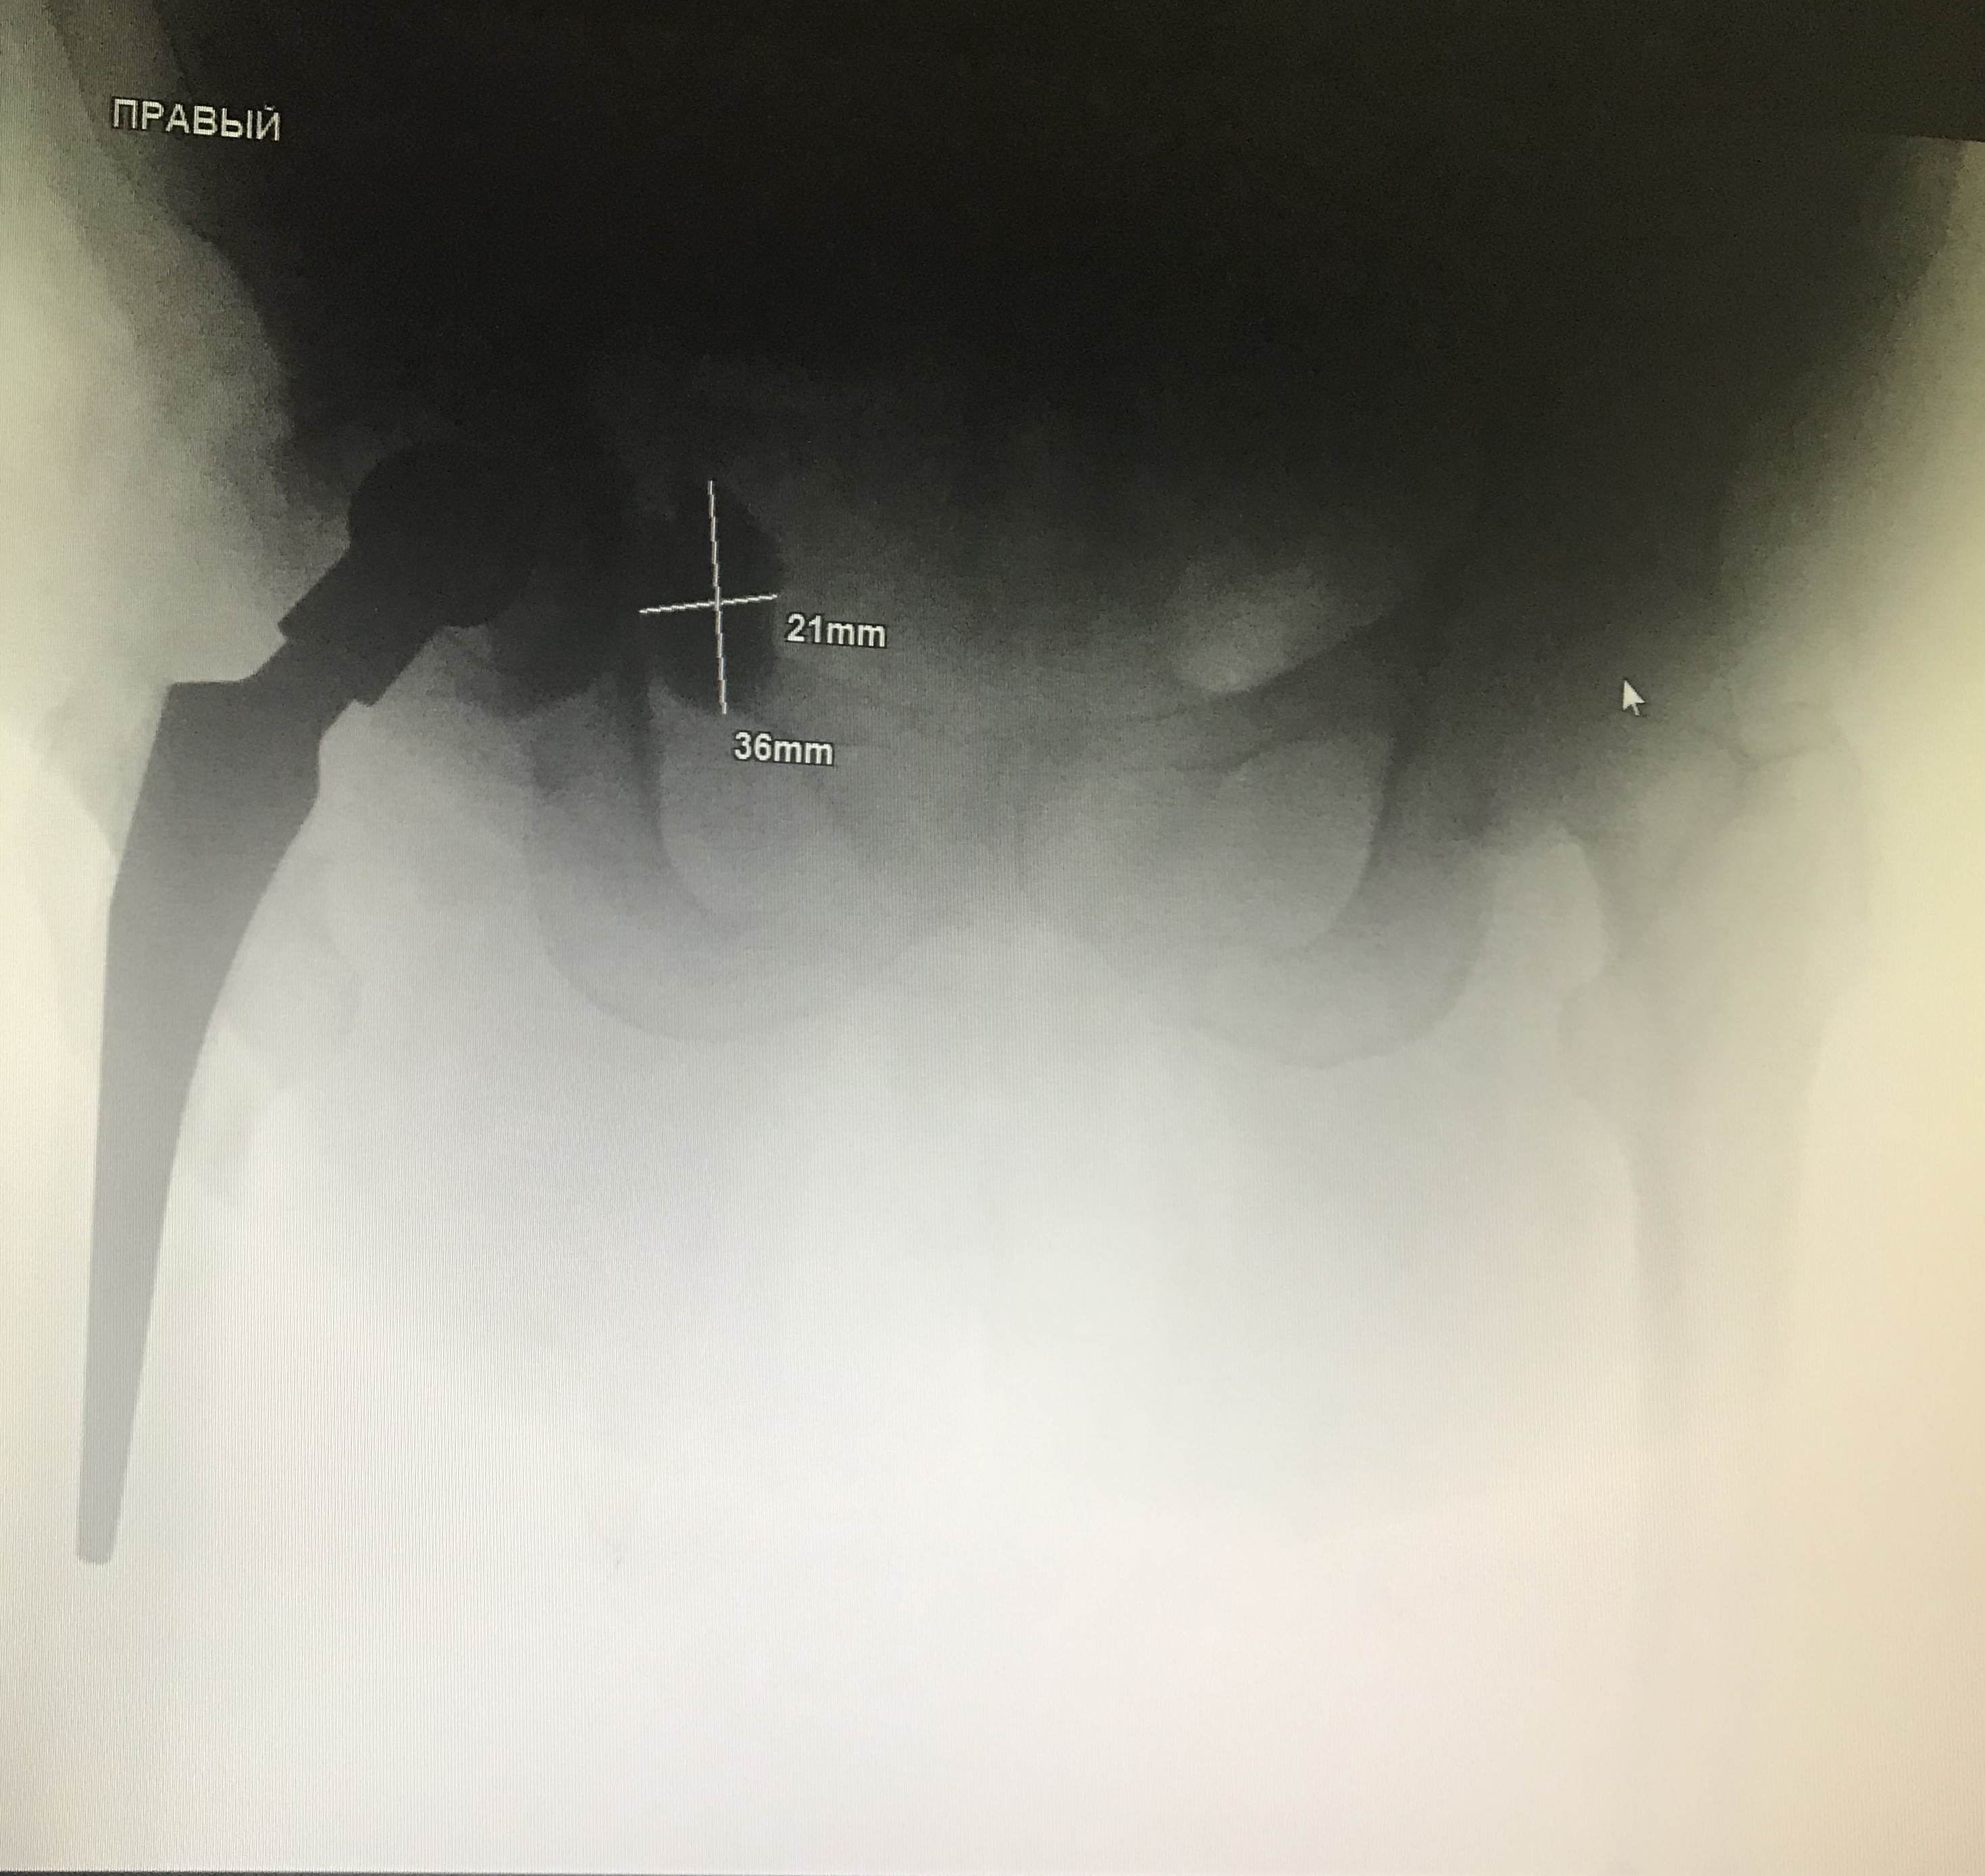

197. Тазобедренный сустав

Поступил экстренно , правый т/б сустав смущает. Что думаете?

Тип: Клиническое наблюдение

Область: Другое

Модальность: Rg

Дата: 16.04.2019 - 10:59